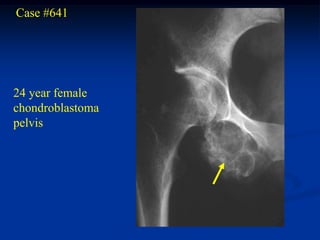

Case #641

24 year female

chondroblastoma

pelvis

CT scan

Another CT cut

Photomic